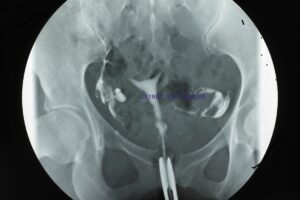

HSG, kısırlık araştırmalarında yaygın olarak kullanılan bir görüntüleme yöntemidir. Bu işlemde, rahim ağzından özel bir kateter yardımıyla rahim boşluğuna kontrast madde (boya) verilir ve eş zamanlı olarak röntgen görüntüleri alınır. Bu sayede, rahim boşluğunun şekli, rahim içinde yer kaplayan lezyonlar (polipler, miyomlar, yapışıklıklar) ve fallop tüplerinin açık olup olmadığı veya tıkanıklık olup olmadığı detaylı bir şekilde incelenir. Ancak HSG’yi sadece mekanik bir değerlendirme aracı olarak görmek, bu işlemin potansiyelini küçümsemek olur. HSG, kadının üreme sistemindeki gizli kalmış sorunları açığa çıkaran, adeta bir “keşif yolculuğu” sunar. Bu yolculukta, hekimler ve hastalar, rahim ve tüplerin “sessiz dili”ni anlamaya çalışır.